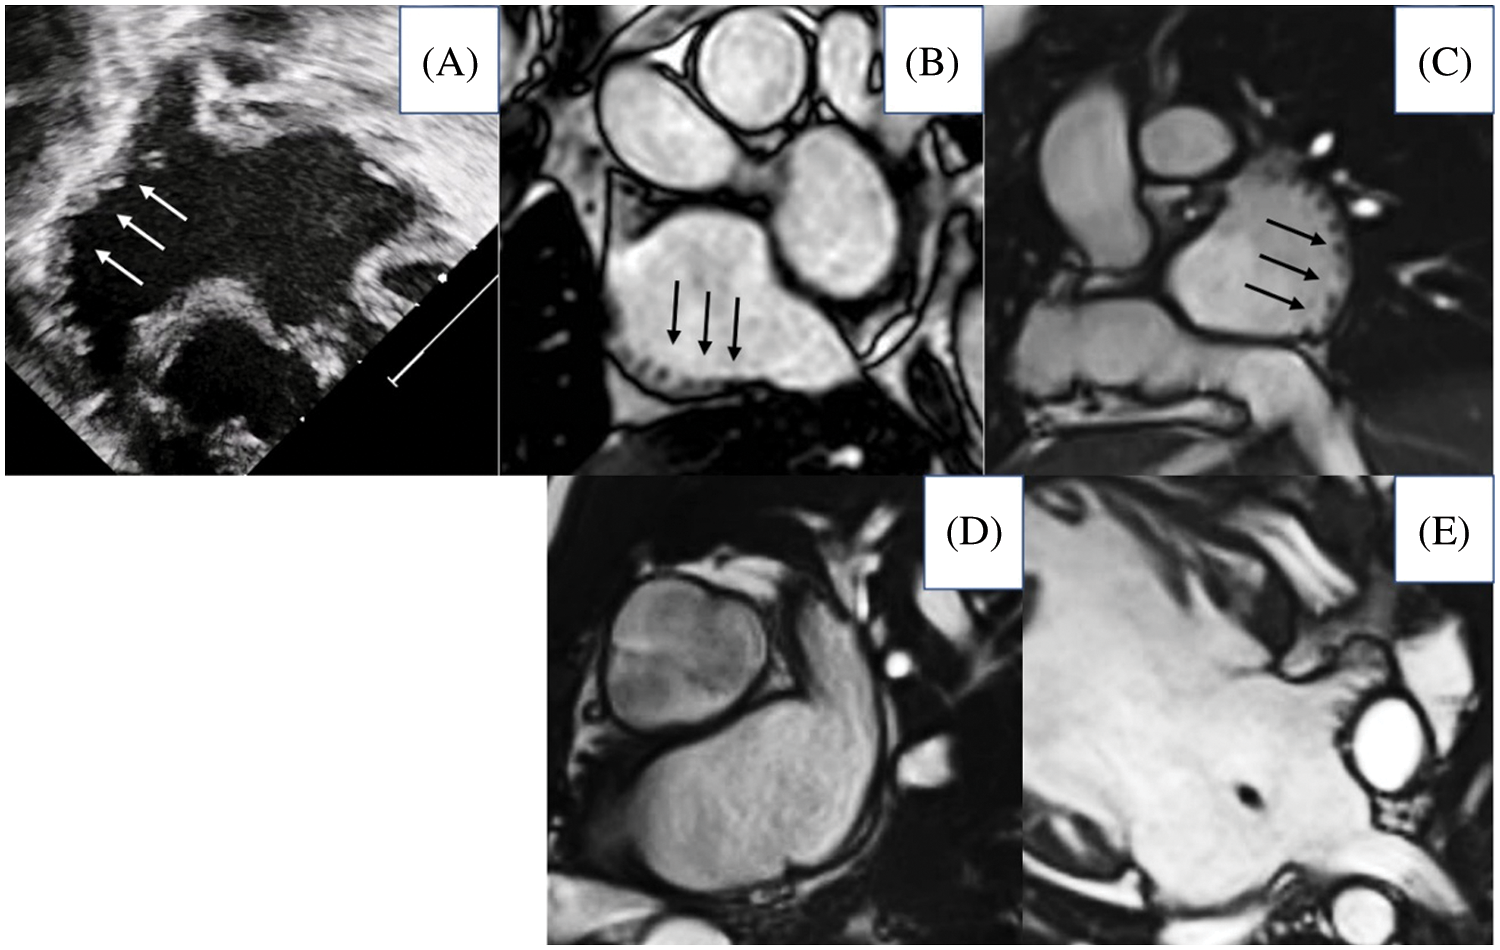

We classified appendages as showing right morphology when presenting with a broad junction with the remainder of the atrial chamber, and with the pectinate muscles within the appendage encircling the atrioventricular vestibule to reach the crux cordis [14]. Left morphology was diagnosed in presence of a narrow junction between the appendage and the remainder of the atrium, and with a smooth vestibule interposing between the extent of the pectinate muscles and the crux (Fig. 1).

Figure 1: Morphology of atrial appendages based on the extent of pectinate muscles. The upper panels show morphologically right appendages (A, ultrasound imaging; B–E magnetic resonance imaging, arrow pointing pectinate muscles extending all along the atrial wall); the lower panels show morphologically left appendages

The point of clinical distinction between the appendages is key, since it is this feature which dictates cardiac isomerism. In our study, we were able to characterize morphology of the appendages with certainty in only two-thirds of patients. This may be due to the fact that we adhered strictly to the notion that the shape of the appendages was insufficient to attribute right or left morphology. Instead, we tried, as far as possible, to use the feature of the extent of pectinate muscles within the appendages relative to the atrioventricular junctions, as is the case for morphologists when holding the hearts in their hands [5]. Echocardiography in neonates can offer useful signs regarding shape adequately to characterize atrial morphology (Fig. 1) [20]. Assessment of the extent of the pectinate muscles, or presence of terminal crests, however, may not be always possible during life for several reasons, since the images provided may not be sufficiently clear, patients have already undergone multiple surgeries, often inducing some kind of volume overload. When seeking to assess the pectinate muscles, our rate of discrimination was lower compared to the findings reported by Yim et al. [9]. Morphologists are usually able to define the anatomy of the appendages in all hearts with so-called heterotaxy. In the investigation of Frescura et al. [21], a perfect agreement was then found between the arrangements of appendages, the bronchuses, and the abdominal organs. Tremblay et al. [22], in contrast, who examined almost 200 hearts with unequivocal isomerism of the appendages, in keeping with our observations, found discordances between the atrial and bronchial patterns.